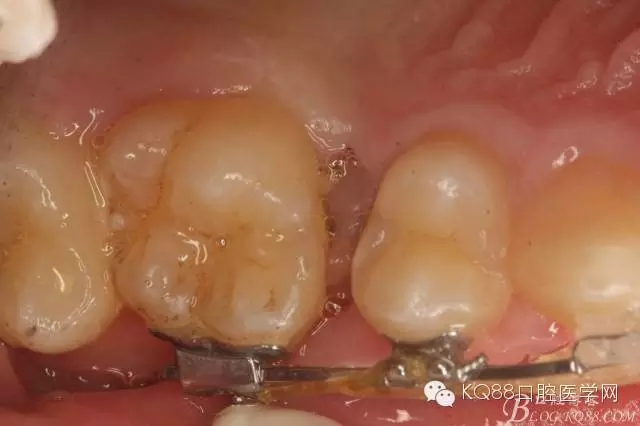

图1.术前患者的口内照片:16与14之间有约2mm间隙,矫治器已经安装到位。

图2.从合面观:16与14之间的牙间隙牙龈颜色异常,建议拍根尖片。